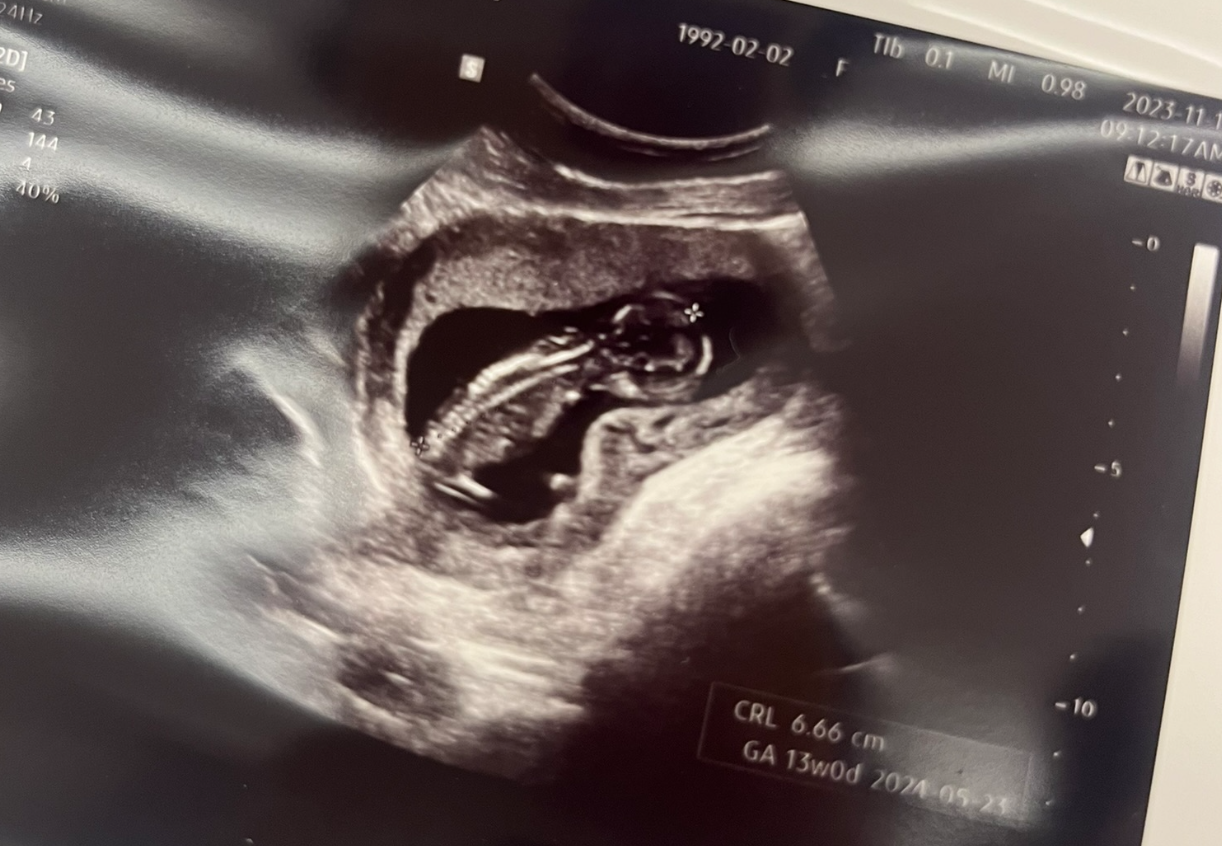

12주차 초음파 사진을 보니 우리 띠용이도 어엿한 사람의 모습을 갖추고 있었다.

너도 열심히 크고있구나, 아빠도 열심히 노력한단다...T^T

12주차에 열심히 엄마 양수에서 헤엄치는 모습을 보고 있자니, 웃음이 절로 나온다.

(이제 나도 아빤가 보다, 생명의 신기함을 느낀다.)

와이프 말로는 애기가 잘 움직이지 않아, 사탕을 먹었더니 그 뒤로 잘 움직인다고 얘기를 전해들었다.

# 임신 13주차

13주차 정도 되니까 이제 입덧도 예전만큼 심하지는 않는데,

그 대신, 띠용이가 커지는 바람에 엄마의 방광을 자꾸 누르나보다.